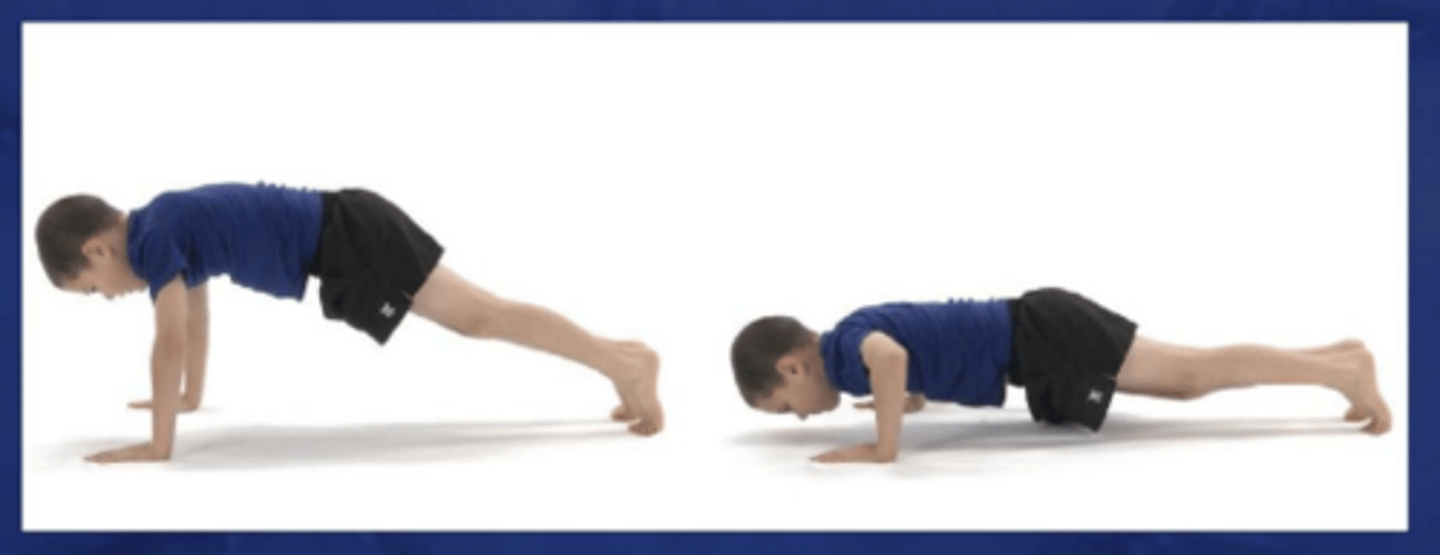

6. Press up

8. Push up

Press ups

What does the image show?

Push ups

What does the image show?